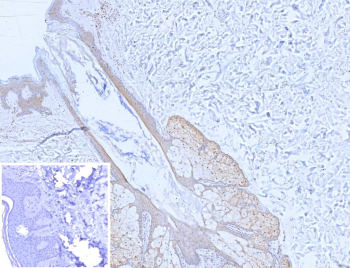

Immunohistochemistry analysis of Mammary Serine Protease Inhibitor / MASPIN antibody (clone SERPINB5/12556) in human skin tissue. FFPE human skin shows HRP-DAB brown staining predominantly in epidermal keratinocytes with both nuclear and cytoplasmic localization, consistent with epithelial expression of SERPINB5. Dermal stromal cells are largely negative. The inset image shows PBS used instead of primary antibody as a negative control. Heat induced epitope retrieval was performed in 10mM Tris with 1mM EDTA, pH 9.0, for 45 minutes at 95oC followed by cooling before staining.